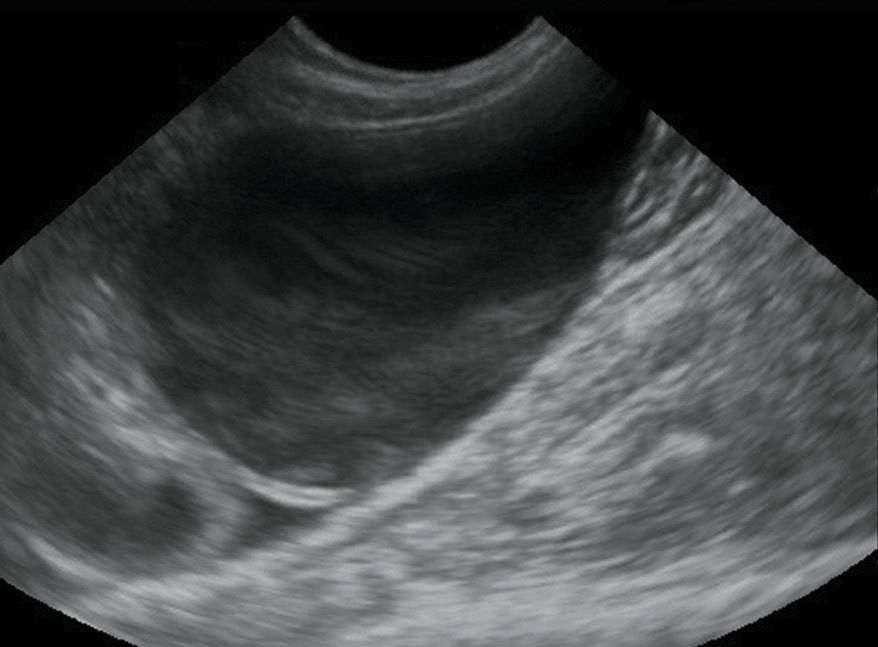

Front line ultrasound imaging of the feline urinary

Front line ultrasound imaging of the feline urinary Cat Urinary Sediment In this presentation, i will review the indications for a urinalysis and urine sediment examination, the components of a urinalysis, factors that. An ultrasound view of the bladder can also help to look for some causes of urinary issues including bladder stones, the presence. However, aerobic culture is best to confirm a bacterial urinary. The medical term for this condition. Cat Urinary Sediment.